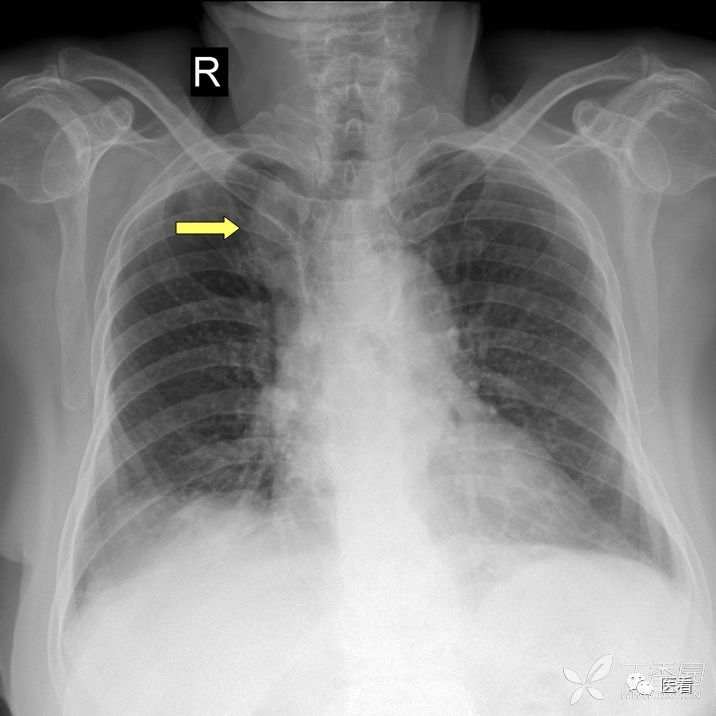

火眼金睛辨真伪:申请单病情摘要:男,44岁,胸痛两天,查体无特殊。

看上去是心脏普遍增大。细心观察,右肺门及右下肺动脉影被掩入增大的心影内(蓝箭头)

本例为食管癌手术后,服用钡餐后,显示实际为胸腔胃(红箭)形成的假象。

真正的心脏增大,肺门及下肺动脉影被向外推移(蓝箭头),在心影外